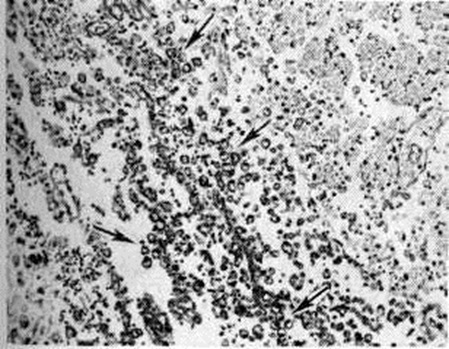

Инфаркты различают по степени геморрагического компонента: белые (серые) инфаркты представлены бледной, дряблой тканью, они составляют 85—90% общего числа инфарктов и могут возникать в любых отделах мозга (рисунок 11 и 12). Геморрагические красные инфаркты имеют вид небольших очагов красного цвета, локализуются только в сером веществе, обычно в коре (рисунок 13), нередко возникают при тромбоэмболиях. Смешанные инфаркты состоят из белых и красных участков, причём последние располагаются преимущественно в лучше васкуляризуемом сером веществе (рисунок 14). При всех видах инфаркта микроскопическое исследование в начальном периоде Инсульт выявляет изменения мозга, обусловленные ишемией: патологию нервных клеток (прежде всего их ишемические изменения — рисунок 15), некробиотические изменения глии. Сосуды более устойчивы к ишемии. Встречаются диапедезные кровоизлияния из мелких сосудов — в очагах серых инфарктов они невелики и единичны, в очагах красных инфарктов и отдельных участках смешанных — они множественные, сливаются между собой. К концу первых суток возникает миграция лейкоцитов, ферменты которых участвуют в расплавлении некротизированной ткани (начало «размягчения»), на 2—3-и суток присоединяется процесс «уборки»; появляются зернистые шары с жиром (рисунок 16), тучные астроциты; организация очага сопровождается пролиферацией волокнистых астроцитов, новообразованием сосудов и коллагеновых волокон и заканчивается образованием глиомезодермального рубца при небольших очагах или соединительнотканных рубцов и многокамерных кист при обширных очагах (рисунок 17). Иногда при стойкой неврологический симптоматике макроскопически не удаётся обнаружить очага полного некроза или рубца; микроскопическое исследование при этом выявляет очаг неполного некроза в коре (гибель нейронов с заместительным астроглиозом).

Электронно-микроскопическое исследование коры мозга человека при Инсульт выявляет различные ультраструктурные изменения нейронов, глиальных элементов и капилляров. В ультраструктуре капилляров можно выделить следующие основные патологический изменения: дистрофию стенки капилляра с накоплением в ней лизосомальных включений, липофусциновых гранул, распадом митохондрий, расслоение и вакуолизацию базальной мембраны (рисунок 18). Кроме того, отмечается разрастание и гиперплазия эндотелия. Ультраструктурные повреждения капиллярной стенки сопровождаются разнообразными изменениями из просвета. Обнаруживается ряд изменений основных субмикроскопических компонентов нейронов. Наиболее характерны нейроны, изменённые по гиперхромному типу (рисунок 19), что сочетается с пикнозом ядра, разрушением митохондрий, деструкцией гранулярного и агранулярного ретикулума, наличием большого числа вакуолей и лизосомальных включений, и нейроны с явлениями хроматолиза (рисунок 20), который сопровождается исчезновением цитоплазматических включений, растворением мембранных структур, образованием вместо цистерн ретикулума групп дискретных пузырьков, отсутствием рибосом, набуханием митохондрий, появлением вакуолей. Изменение ультраструктуры капилляров и нейронов сопровождается отёком астроцитарных отростков, скоплением тел глиальных клеток вокруг патологически изменённых элементов. В области расположения патологически изменённого капилляра наблюдаются клетки-тени (клетки в состоянии кариоцитолиза). Прослеживается зависимость изменений элементов одной цепи: нейрон — капилляр — глия.